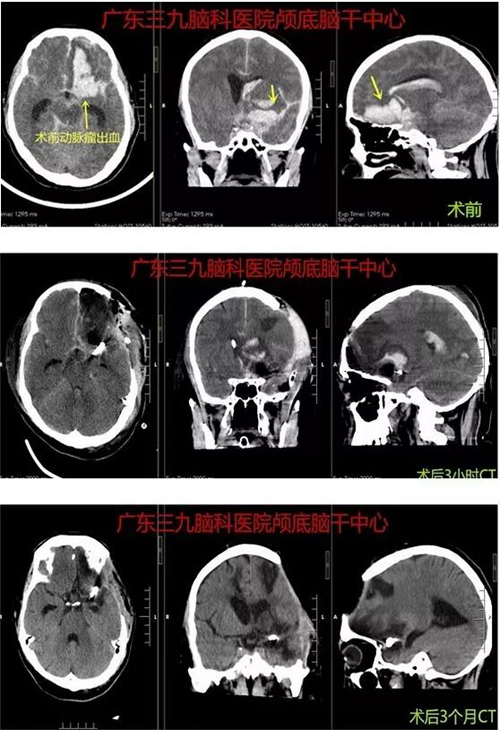

患者王某,男,49岁。因“突发头痛、呕吐伴意识不清1天余”于2018年10月28日入院。患者于26日晚饭后无明显诱因出现头痛,未行相关检查,于当地诊所输液治疗,具体不详,自诉稍好转。27日晚出现突发晕倒,伴多次呕吐,逐渐意识障碍,门诊查头颅CT示:左侧额颞叶脑出血并破入脑室、蛛网膜下腔出血,为进一步治疗转入广东三九脑科医院神经外一科,于28日行“大脑中动脉瘤夹闭术”,术程顺利,术后患者恢复好,对答切题,右侧肢体肌力4级,左侧肢体肌力5级。

▲图1:术前CT示广泛蛛网膜下腔出血,左侧额叶血肿形成

▲图3:术后当天CT示动脉瘤夹闭术后改变